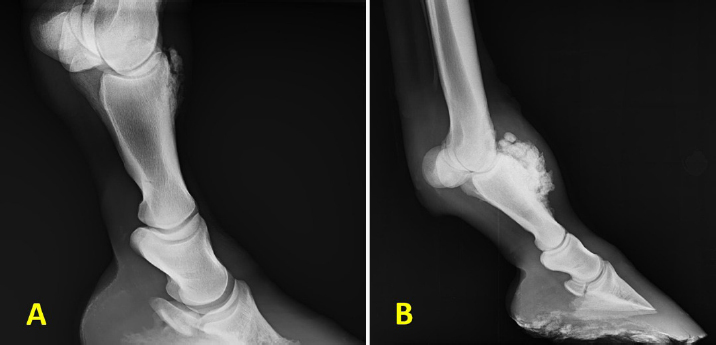

The radiological examination revealed a new bone formation involving the dorso-proximal aspect of P1 (Fig. 2A and B). The size of the newly formed bone was variable among cases. No other abnormal radiographic findings were noted in the horses. In two cases, the exostosis was extended proximally to include the dorsal aspect of the distal extremity of Mc3 (Fig. 3A). In one of the two cases, there were multiple fragments in both P1 and Mc3 exostosis (Fig. 3B).

Fig. 3. Radiographic findings in two different Sarj horses with forelimbs P1 and Mc3 bone exostosis. (A) Lateromedial radiograph shows a new bone formation involving the dorso-proximal P1 and disto-dorsal Mc3. (B) Lateromedial radiograph a new bone formation involving the dorso-proximal P1 and the disto-dorsal Mc3. There are multiple bone fragments close to the newly formed bone lesions, which seem to be from the lesion. P1: first phalanx bone; Mc3: third metacarpal bone.